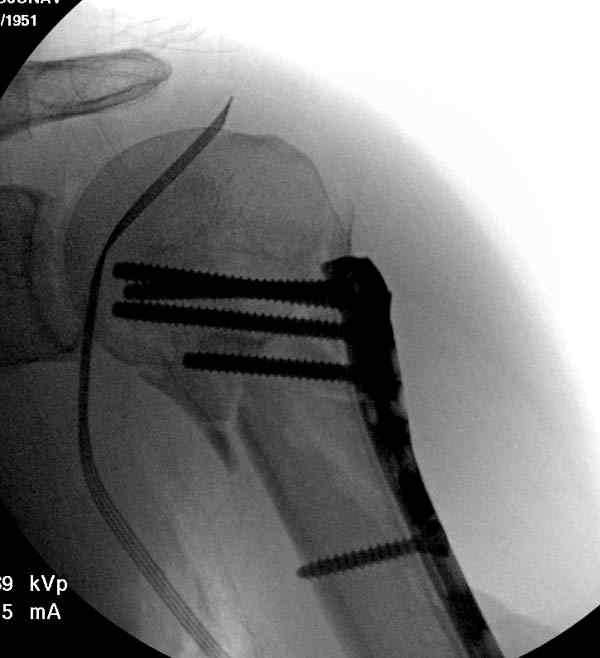

Здесь пример открытой репозиции 57 летнего с переломом плеча (1,2) смещение обнаружено на интероперационном снимке. При нормальной прямой проекция (3) угловое смещение обнаружили в аксиальной проекции (4)

После устранения смещения пластина установлена выше (5,6,7) и финальные снимки (8,9,10)

Подбор импланта тоже имеет значение, например многие импланты направлены для фиксации перелома без учета ротаторной манжетки. Предпочтительными являются низко сидящие полиаксиальные пластины, где верхние шурупы можно проводить под углом в 120 градусов. (11)

Пластина от Synthes или ее копии (надеюсь простят критику друзья из Деоста) считаются трудным из-за обширности доступа, особенно при установке верхне-заднего шурупа, где доступ надо расширять в верхнем отделе до ротаторной манжетки. Верхне сидящие импланты предназначены для проведения опоры (buttress) за бугристость плеча, но тогда приходится сталкиваться с подакромиальным импинжментом.